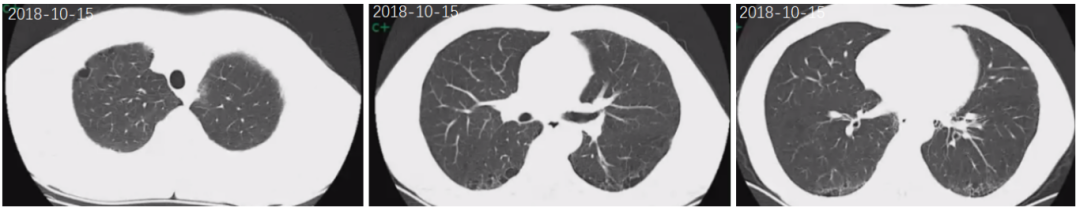

第一阶段:患者2018-10-15至我院体检查胸部CT示双肺胸膜下为主的间质性病变伴肺部结节(图1)。当时查血免疫系列示ANA、ANCA、AMA、肌炎谱均阴性。考虑为特发性肺纤维化(IPF),建议密切门诊随访,2019-2023年间患者因新冠病毒流行未规律复诊,自我感觉良好。

image.png

图1 2018-10-15体检胸部CT示双肺胸膜下为主的间质性病变伴肺部结节